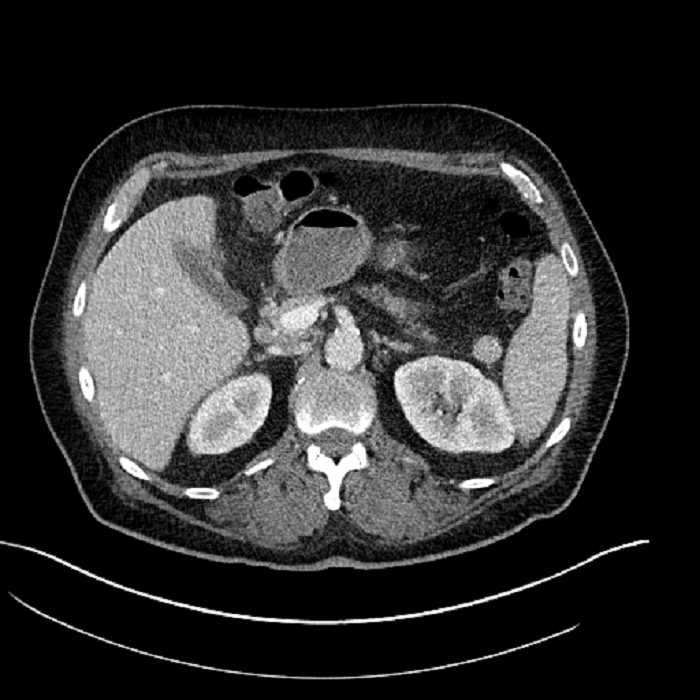

Age: 63

Sex: Male

Indication: Abdominal pain

• Large fluid density structure in hepatic segments 7 and 8 measuring 10 x 7 x 7 cm with internal septation and circumferential ill-defined low density compatible with edema

• Peripherally enhancing subcapsular collections along the anterior margin of the left hepatic lobe measuring 3 x 1 cm and 2 x 1 cm

• Clearly marginated fluid density structure in segment 7 and several other scattered tiny hypodensities, which likely represent cysts

• Hepatic abscess

Acute sigmoid diverticulitis complicated by a small contained perforation and a large abscess in the right hepatic lobe. Additional small subcapsular abscesses along the anterior margin of the left hepatic lobe.

• The classic CT imaging appearance is a double target sign with internal low density surrounded by an internal enhancing rim (capsule) and a low density external rim (edema)

• Abscesses may be unilocular or multilocular

Hepatic abscess showing the double target sign with low density internally surrounded by a thin inner enhancing rim (red arrow) and ill-defined outer low density rim (yellow arrow). Blue arrow indicates an internal septation. Red arrows: additional smaller subcapsular abscesses. Red arrow: focal contained perforation associated with diverticulitis.